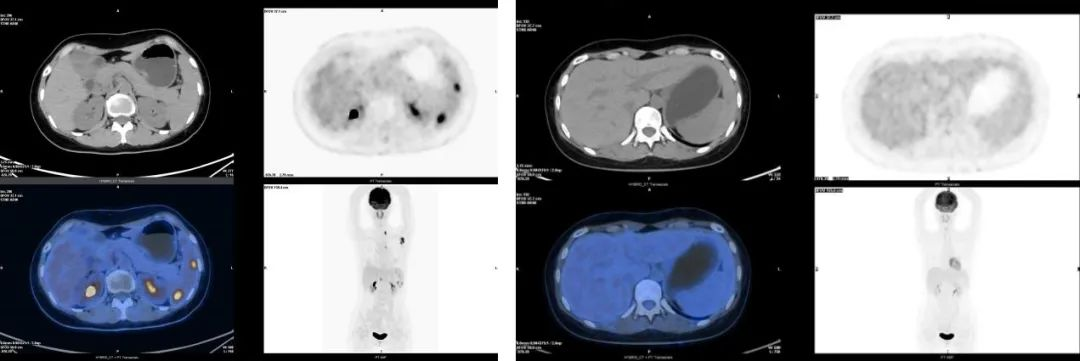

➤PET-CT示左锁骨上、左腋窝、肝门、腹膜后多发肿大淋巴结,于相应部位见异常放射性浓聚影,Deauville评分5分,考虑淋巴瘤复发;脾肿大,于相应部位见结节状异常放射性浓聚影,Deauville评分5分,考虑淋巴瘤浸润;双颈多发淋巴结,于相应部位见淡淡放射性浓聚影,考虑淋巴瘤可能性大;双肺间质性肺炎;纵隔淋巴结增生;左侧胸膜稍增厚;双侧股骨头缺血性坏死。

➤2021.12起,予BV联合苯达莫司汀治疗,2个周期后疗效评估为部分缓解(PR),4个周期后达CR,查PET-CT示原左锁骨上、左腋窝肿大淋巴结较前明显缩小/减少,于相应部位见淡淡放射性浓聚影,Deauville评分2分,考虑淋巴瘤治疗后局部肿瘤细胞处于代谢抑制状态;脾稍大,于相应部位未见异常放射性浓聚影;原肝门、腹膜后淋巴结已不明显;多个颈、胸、腰椎骨质密度增高大致同前,于相应部位未见异常放射性浓聚影;纵隔淋巴结增生、左侧胸膜稍增厚同前。